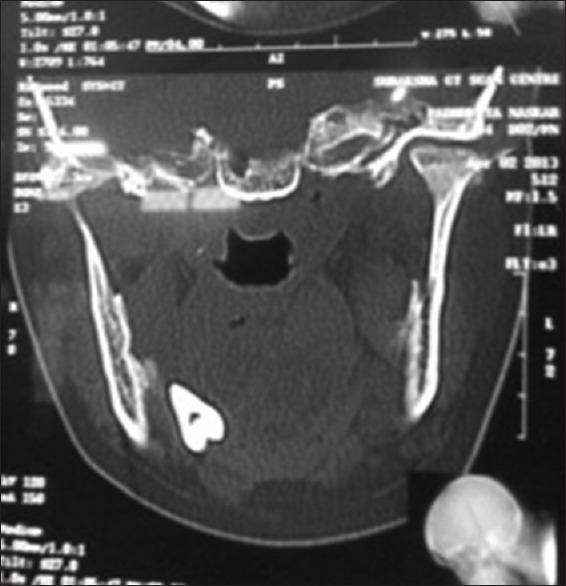

Iatrogenic displacement of a tooth or tooth fragment is a rare but well-recognized complication that occurs during exodontia. The most common sites of dislodgment of a mandibular third molar fragment are the sublingual, submandibular, and pterygomandibular and lateral pharyngeal spaces. Removal of a displaced tooth from these spaces may be complex due to poor visualization and limited access. A thorough evaluation of all significant risk factors along with precise localization of the tooth by clinical and radiographic means should be performed to prevent untoward complications. This paper reports two cases of iatrogenic displacement of mandibular third molar teeth, in the sublingual space and lingual pouch. Both the cases were managed intraorally under general anesthesia, and the postoperative healing was satisfactory and uncomplicated. A brief review of literature is also provided in this paper.

摘要

牙齿或牙碎片的医源性移位是拔牙过程中一种罕见但已被充分认识的并发症。下颌第三磨牙碎片最常见的移位部位是舌下、颌下、翼下颌和咽旁间隙。由于视野不佳和操作空间有限,从这些间隙取出移位的牙齿可能很复杂。应通过临床和影像学手段对所有重要危险因素进行全面评估,并精确确定牙齿位置,以预防不良并发症。本文报告了两例下颌第三磨牙医源性移位至舌下间隙和舌袋的病例。两例均在全身麻醉下经口处理,术后愈合良好,未出现并发症。本文还对相关文献进行了简要综述。